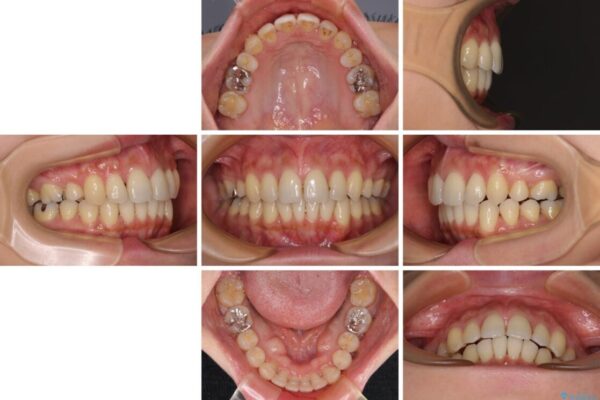

治療途中

• 上顎前歯の突出を軽減 インビザラインによる抜歯矯正 治療途中画像